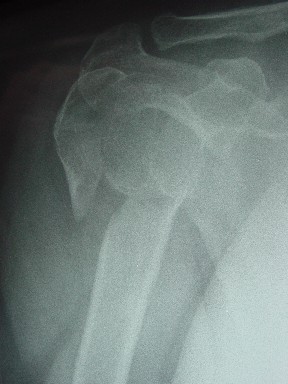

Женя, а как ты водишь спицы, в смысле, как делаешь входное отверстие, и как в него проводишь V-спицу? А то о дна из спиц, та, у которой не дошла до головки одна палочка буквы V, как-то выглядит на рентгенограмме, как будто или через очень большое отверстие введена, или каждая половинка через отдельные отверстия.

В чем ты видишь причину вторичного смещения?

Мне кажется, проблема в том, что не все концы спиц зашли в головку, и зашедшие - недостаточно далеко прошли.